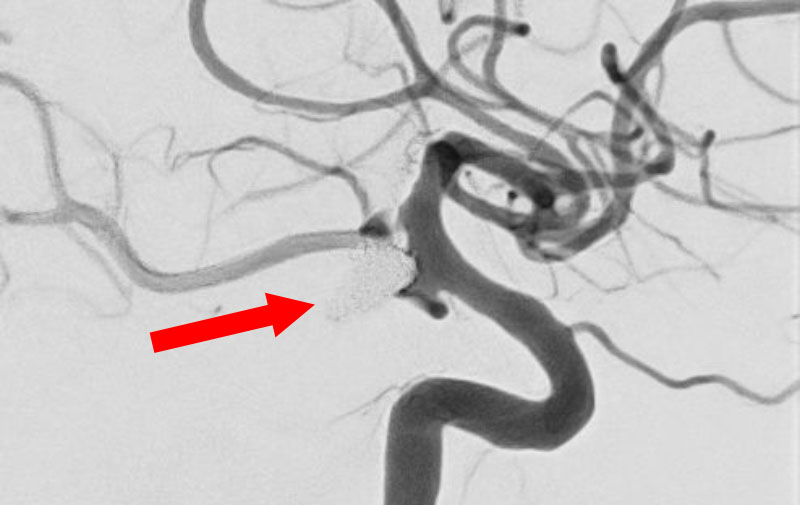

'25年10月

左総頚動脈狭窄症

30代

院内外来

No.1590 手術前

No.1590 手術中

No.1590 手術後